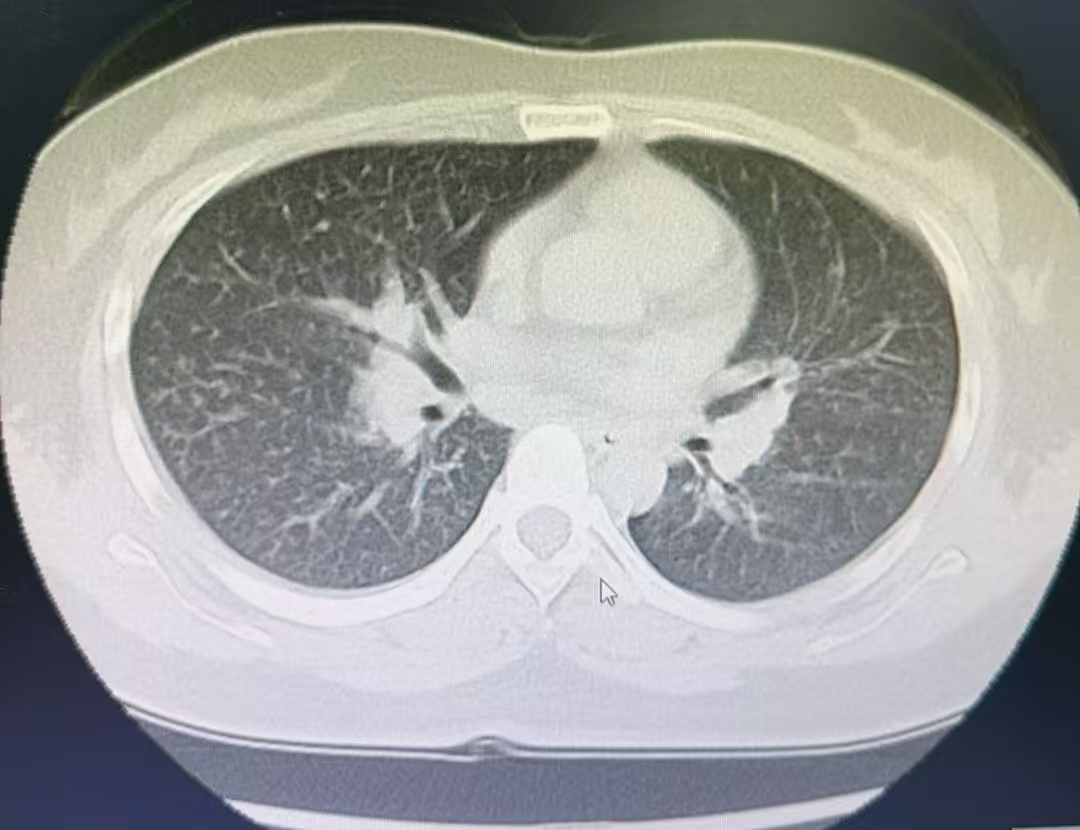

约一个月前张女士迟缓出现胸闷气喘、呼吸艰巨等症状。医师会诊其患上了“急性嗜酸性粒细胞肺炎”这种陌生病。

江苏省淮安市第二东谈主民病院呼吸与危重症医学科副主任医师何远强先容:84消毒液主要要素是次氯酸钠,具有强氧化性和腐蚀性 ,84消毒液蒸发的氯气被吸入呼吸谈后,会与气谈粘膜水分生成次氯酸钠和盐酸,刺激呼吸谈的粘膜,引起患者咳嗽气喘呼吸艰巨等症状。始终走漏可能导致化学性支气管炎,急性嗜酸性粒细胞肺炎,以至肺水肿间质性肺炎,呼吸清寒等严重并发症。

图片着手:淮安市第二东谈主民病院